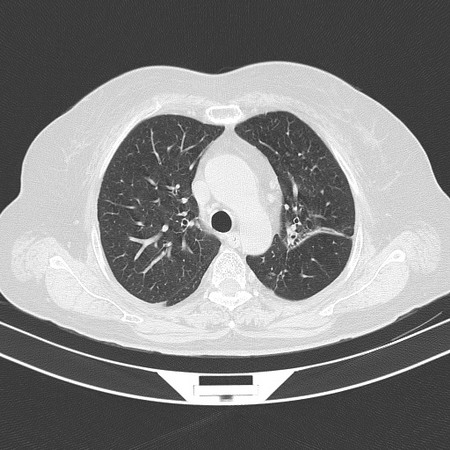

以下是引用sdzyy在2008-11-21 14:57:00的发言:[br]右肺结节影,建议定期复查!支扩,左侧叶间胸膜增厚.

以下是引用卜一在2008-11-21 14:40:00的发言:[br]炎性结节可能!建议定期复查!另:支气管扩张征伴感染!

以下是引用guanaishengming在2008-11-21 17:26:00的发言:[br]右肺结节影,建议定期复查!